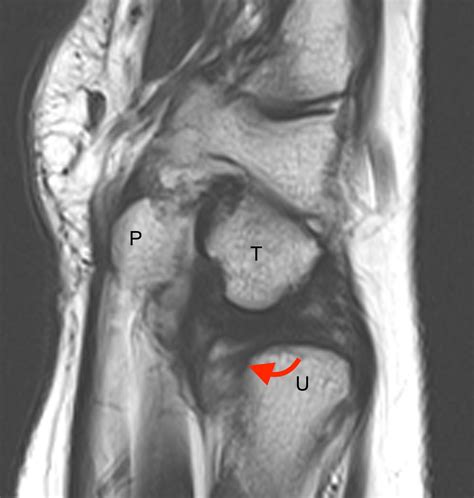

• Imaging Tests: X-rays, MRI, or CT scans may be ordered to visualize the knee joint and confirm the diagnosis. MRI is particularly useful for detecting soft tissue injuries like cartilage tears.